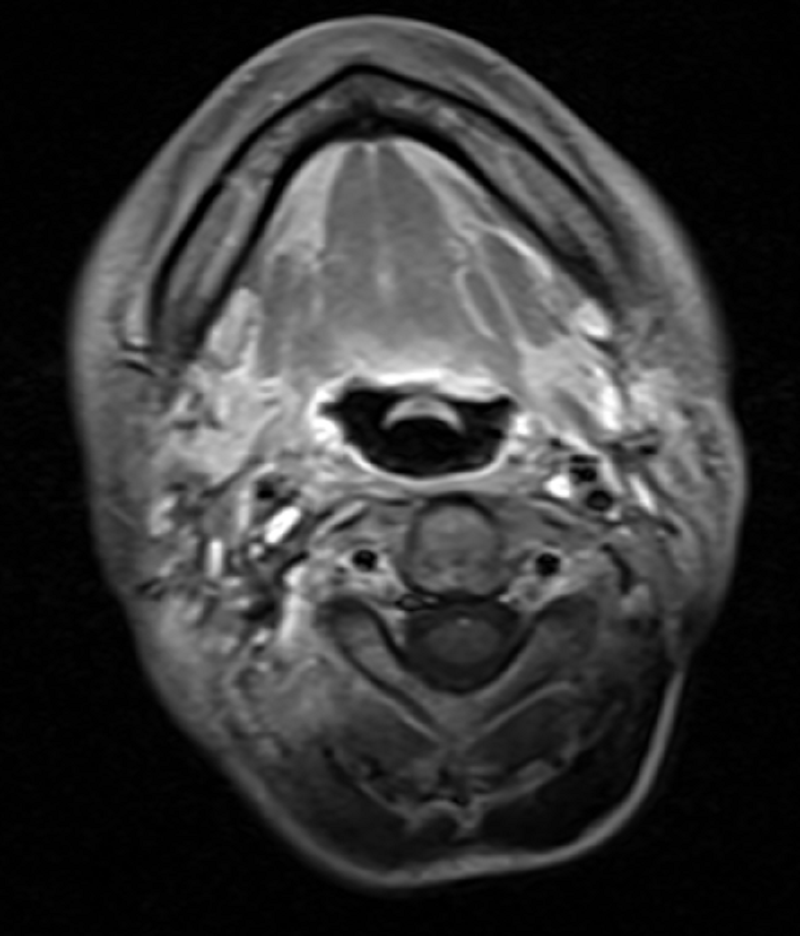

自2020年7月小萍确诊鼻咽癌并颈部淋巴结转移后至肿瘤科二区就诊至今,生存期已达3年时间,且极大地改善了生活质量。2023年6月,小萍复查肿瘤消退无复发,病情稳定。

2023-06-15鼻咽部MRI,肿瘤消失无复发